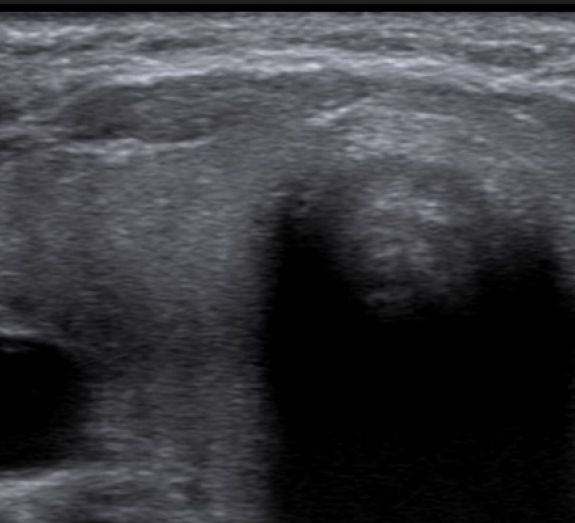

Schilddrüsenultraschall

Hierbei werden das Volumen, die Binnenstruktur, eventuelle Knoten und der Durchblutungsgrad Ihrer Schilddrüse untersucht.